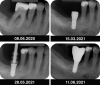

Figures